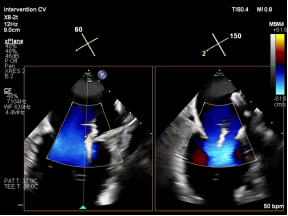

手术中,团队经食管超声心动图(TEE)引导下精准完成房间隔穿刺,为器械操作提供良好空间;建立稳定输送路径,使导向系统与二尖瓣平面充分对齐;利用X-plane及三维超声反复定位脱垂区域,微调器械角度,实现对目标瓣叶的精准抓取;确认夹持质量后释放装置,最终完成修复。

【图片2-5:术中TEE、夹持瞬间、术后效果图】

术后即刻评估显示,患者二尖瓣反流由重度(4+)降至轻度(1+),跨瓣压差维持理想范围,肺静脉血流明显改善,手术取得良好效果。